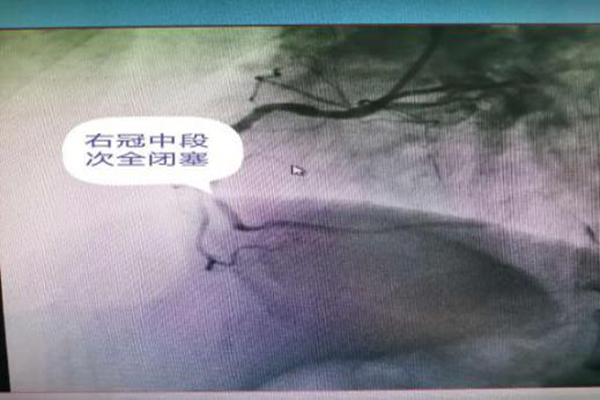

729日早6點(diǎn)起床后胸痛再次發(fā)作,服“速效救心丸也無(wú)緩解。急忙撥打我院120救治,急救醫(yī)生查心電圖示急性下壁心肌梗死,生命垂危,立即上傳我院胸痛中心,醫(yī)護(hù)人員經(jīng)胸痛綠色通道迅速將先生送入導(dǎo)管介入手術(shù)室開(kāi)始搶救。心內(nèi)科郭應(yīng)先主任和許慶華副主任憑借精準(zhǔn)判斷,迅速找到患者的罪犯血管”——右冠狀動(dòng)脈中段閉塞,迅速入一枚支架及時(shí)開(kāi)通先生閉塞的心臟血管。術(shù)中一波三折,球囊擴(kuò)張后出現(xiàn)無(wú)復(fù)流,患者胸痛劇烈,立即給于冠脈內(nèi)溶栓治療,刺破球囊送至病變遠(yuǎn)端造影示病變處出現(xiàn)夾層,立即植入支架,造影示血流恢復(fù),患者胸痛迅速緩解。患者生命體征平穩(wěn)轉(zhuǎn)入了監(jiān)護(hù)病房繼續(xù)治療

右冠中段次全閉塞

支架植入術(shù)后